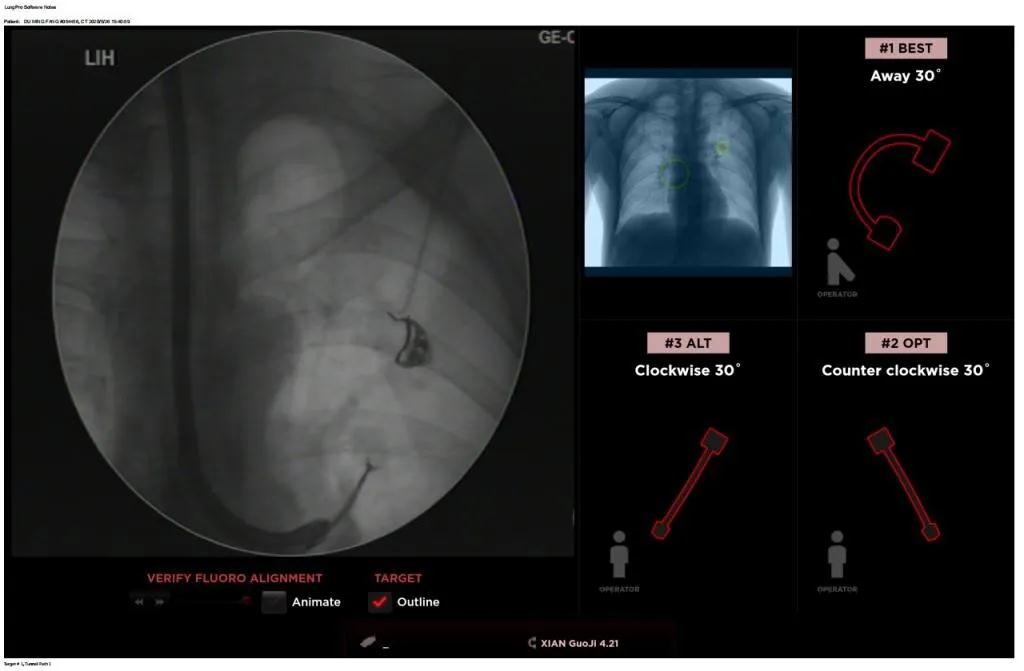

近日,西安國際醫(yī)學(xué)中心醫(yī)院胸科醫(yī)院歐陽海峰副院長完成西北地區(qū)首例LungPro全肺導(dǎo)航系統(tǒng)引導(dǎo)下經(jīng)支氣管鏡跨肺實質(zhì)肺外周結(jié)節(jié)活檢術(shù)。

經(jīng)過充分的討論后,歐陽海峰副院長決定為患者實施LungPro全肺導(dǎo)航系統(tǒng)引導(dǎo)的經(jīng)支氣管跨肺實質(zhì)肺外周結(jié)節(jié)活檢術(shù)。Broncus導(dǎo)航系統(tǒng)LungPro具有全球領(lǐng)先獨創(chuàng)的BTPNA技術(shù)(支氣管鏡下跨結(jié)節(jié)抵達(dá)術(shù)),可以實現(xiàn)對氣道外周孤立性肺小結(jié)節(jié)的精準(zhǔn)定位,建立直接通往氣道外病變部位的通道,以實現(xiàn)全肺的診斷及后續(xù)治療。這項技術(shù)不僅彌補(bǔ)了現(xiàn)有支氣管鏡技術(shù)由于受限于病變部位是否有氣道可通向以及無法準(zhǔn)確定位病變部位而造成的較低診斷率,同時還彌補(bǔ)了CT引導(dǎo)下經(jīng)胸穿刺(TTNA)無法適用于某些特定部位如中央及肩胛骨等結(jié)節(jié)的問題,并且還避免了經(jīng)胸穿刺給患者帶來氣胸、出血的高風(fēng)險,可有效提高肺部結(jié)節(jié)及早期肺癌診斷陽性率,亦可用于早期肺癌的射頻消融或微波治療,具有微創(chuàng)、安全、同期雙肺診療等優(yōu)勢。

團(tuán)隊術(shù)前進(jìn)行了精心的準(zhǔn)備,通過高分辨率CT建立了導(dǎo)航路徑,在麻醉科手術(shù)室的配合下,借助LungPro引導(dǎo)順利的確定了病灶部位、建立隧道并實施活檢,術(shù)后患者恢復(fù)順利出院。